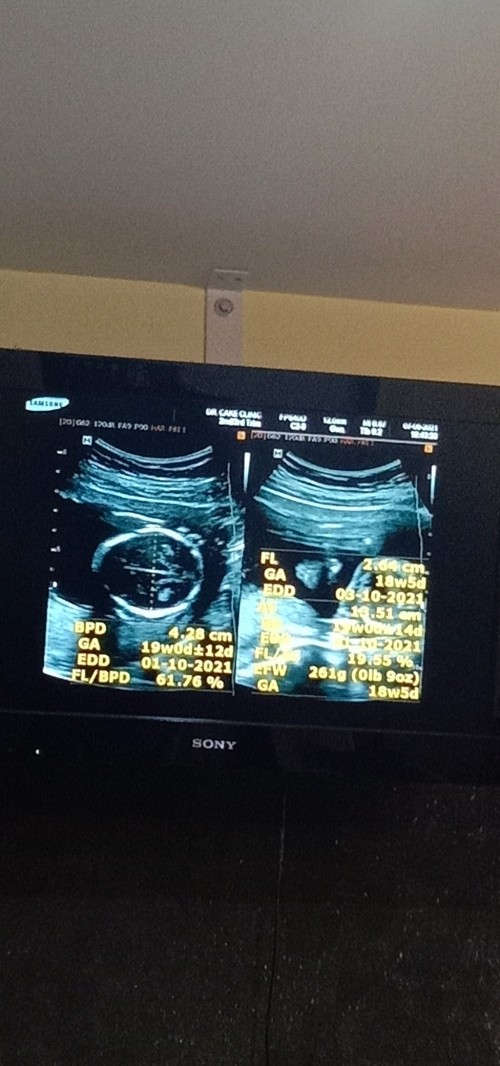

ลุงหมอบอกเหมือนจะ ผญ 😊 19+2 แล้วคะ

บ้านนี้กำหนดคลอด 8 ตุลาคมจร้า

บ้านเด็กชายคับ19w2dน้ำหนัก225ตอน18w5D